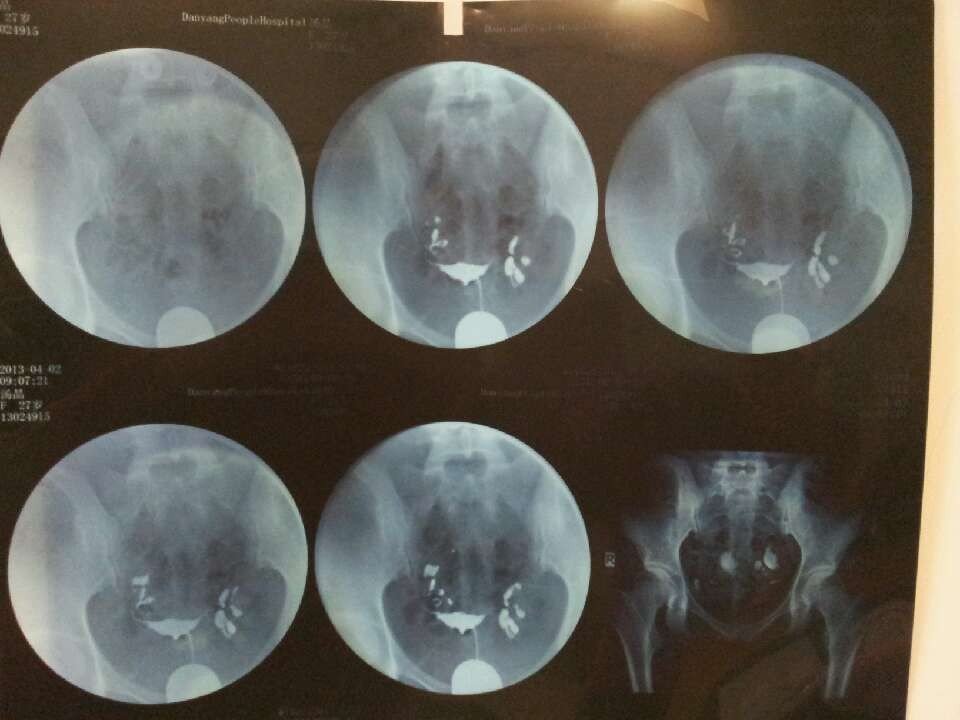

最近造影归来,子宫形态无明显异常,双侧输卵管通畅,双侧输卵管伞不显影无殊!造影剂在盆腔内弥散不佳!

有什么好的治疗方法吗?这个就是盆腔粘连是吗?

你好,造影剂在盆腔内弥散不佳,说明输卵管是存在通而不畅的情况,这个也是会引起受孕困难的,建裕用议尽快在医生的指导下做某殖治疗,一般北贵概是可以治疗好的,无需担心。

您好,很高兴为您解答,您这个属于输卵管伞部粘连。这种情况通液效果不大好,可以手术治疗。